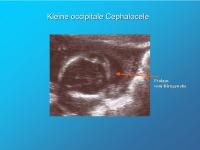

Kleine occipitale Cephalocele

Abbildung 9

Keywords:

Cephalocele